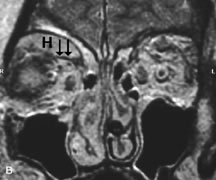

MRI is particularly helpful in the detection and characterization of subperiosteal hematomas of the orbit (Fig. 19). They are most commonly seen in the subperiosteal space of the superior orbit as well-defined masses following a traumatic injury. The signal intensity varies depending on the acute, subacute, or chronic nature of the hematoma, based on the stage of blood degradation. Fresh hemorrhages are hypointense on T1-weighted images and hyperintense on T2 images. Hematomas that are 1 to 7 days old are hypointense on both T1- and T2-weighted images. T1-weighted images of hematomas more than a week old are hyperintense due to the oxidation of deoxyhemoglobin to methemoglobin, whereas the T2 images remain hypointense.63

Fig. 19. A. T1- and (B) T2-weighted MR scans demonstrate a large acute subperiosteal hematoma (H) that lies between the cortical bone of the orbital roof and the inferiorly displaced periorthira (double arrow). The extracopal fat (arrow) and levator muscle are displaced inferiorly.